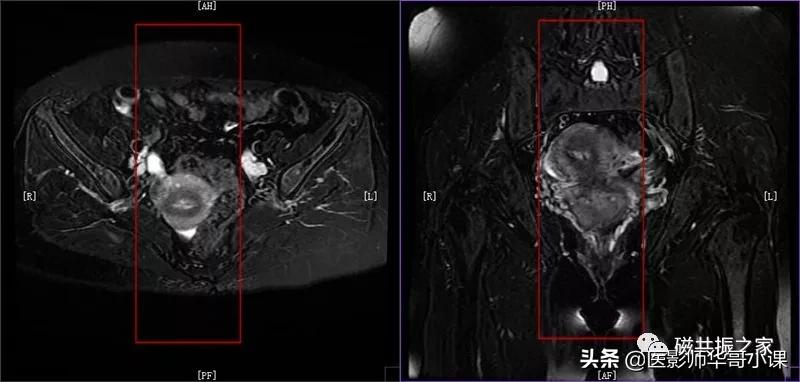

冠状位: COR T2 FS FSE 冠状面T2脂肪抑制序列

在横轴位和矢状位上定位,在矢状位上找到显示子宫全长最好的层面,如需了解宫颈病变,使定位线平行于宫颈管长轴(图A),如需了解子宫内膜病变,使定位线平行于子宫内膜长轴。在横轴位上找到显示子宫最大的层面,使定位线平行于当前子宫内膜长轴,扫描范围包括整个子宫及两侧附件,需包括整个病变范围。

冠状位是显示卵巢及子宫附件较为理想的方位。